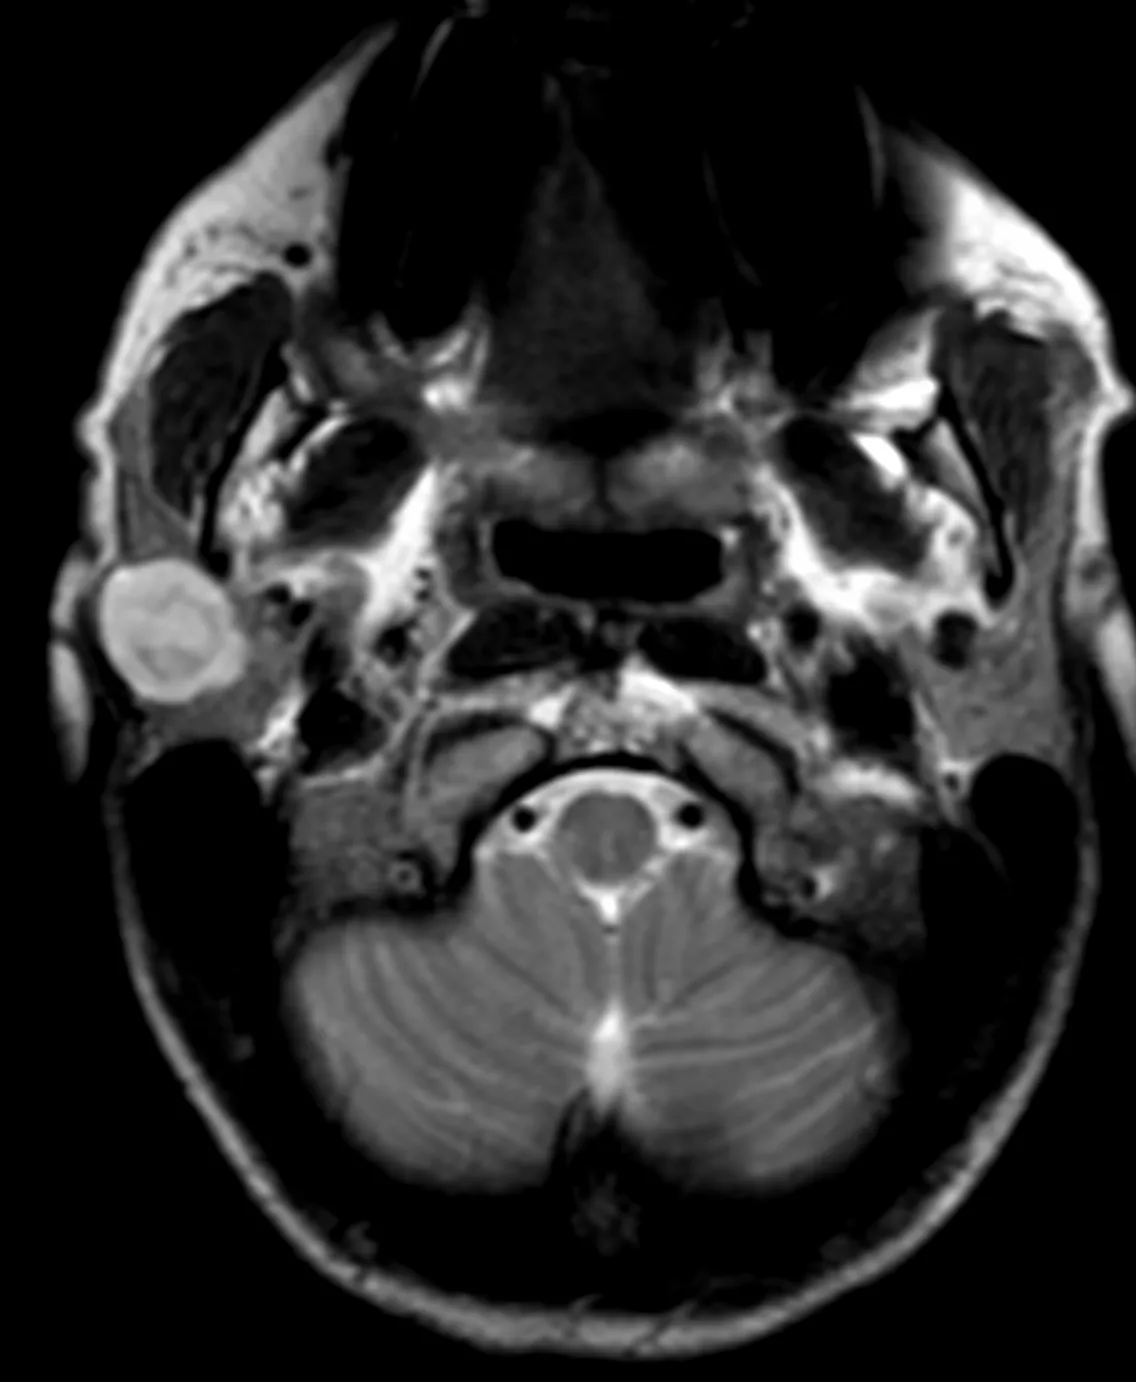

Наконец-то я увидел это воочию! Киста полости Верги, промежуточного паруса, осложнённая гидроцефалией. Из анамнеза: Низкое артериальнео давление, нарушение речи, затуманенное сознание, головная боль, головокружение, в 1989 году перенёс менингит.

А Вы видали такое? Я впервые вижу, раньше только читал в литературе.